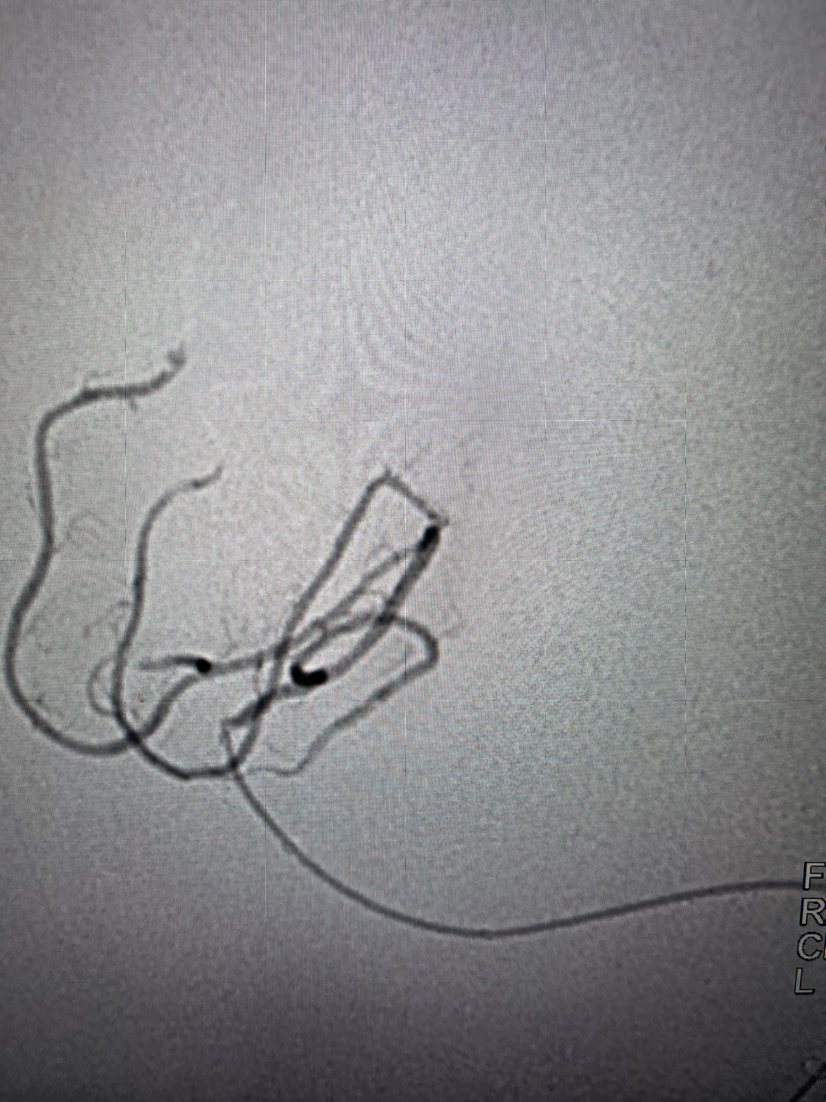

微导丝携带2.0mmx15mmFastunnel输送型球囊扩张导管通过闭塞处造影位于血管真腔

2.0mmx15mmFastunnel输送型球囊扩张导管扩张后零交换扩张后植入TP EP2 4.0X23mm支架